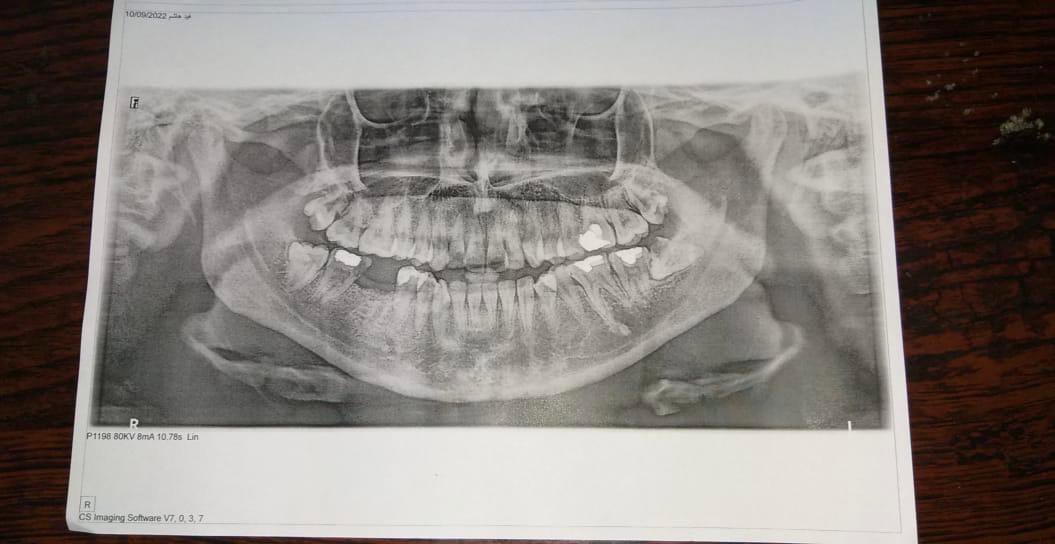

عملية قلع جراحي لسن العقل في عيادة جراحة الأسنان